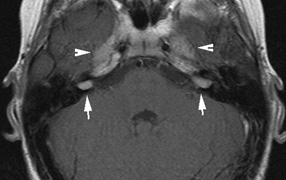

Optic nerve gliomas may involve the optic chiasm and be associated with endocrine disorders or nystagmus.68–70 Surgical excision of chiasmal gliomas (Fig. 6) carries a high risk of visual loss. Invasion of the hypothalamus or the third ventricle carries a poor prognosis, with greater than 50% 15-year mortality rate.71 One review of radiation treatment for chiasmal gliomas collated data from small case series and found no significant long-term improvement in visual function, progression, or mortality with radiation treatment.71 Other reports suggest that radiation doses over 4500cGy improve symptoms and slow progression of chiasmal gliomas over several years.72 Adequate tumor coverage by radiotherapy results in irradiation of normal brain and nearly all children need hormone replacement.73 Chemotherapy is an alternative.74,75

Fig. 6. Surveillance images of a 12-year-old girl with NF1 and an optic nerve glioma which has extended to involve the chiasm. Pre- (a) and postcontrast (b) T1-weighted coronal images reveal a large suprasellar mass with an enhancing component (arrow) seen separately from the normally enhancing pituitary gland. (c) Axial scans through the suprasellar cistern show the tumor is high signal on T2-weighted scans. (d) Enlargement of the chiasm, optic nerve and hypothalamus is visible on the post-contrast T1-weighted sagittal image. Although optic nerve glioma usually has a good prognosis (with visual function often remaining stable in the absence of any intervention66,67), chiasmal involvment is a poor prognostic indicator. A sign of chiasmal involvment may be new onset of endocrine disorders or nystagmus. Surgical excision of chiasmal gliomas carries a high risk of visual loss.68–70